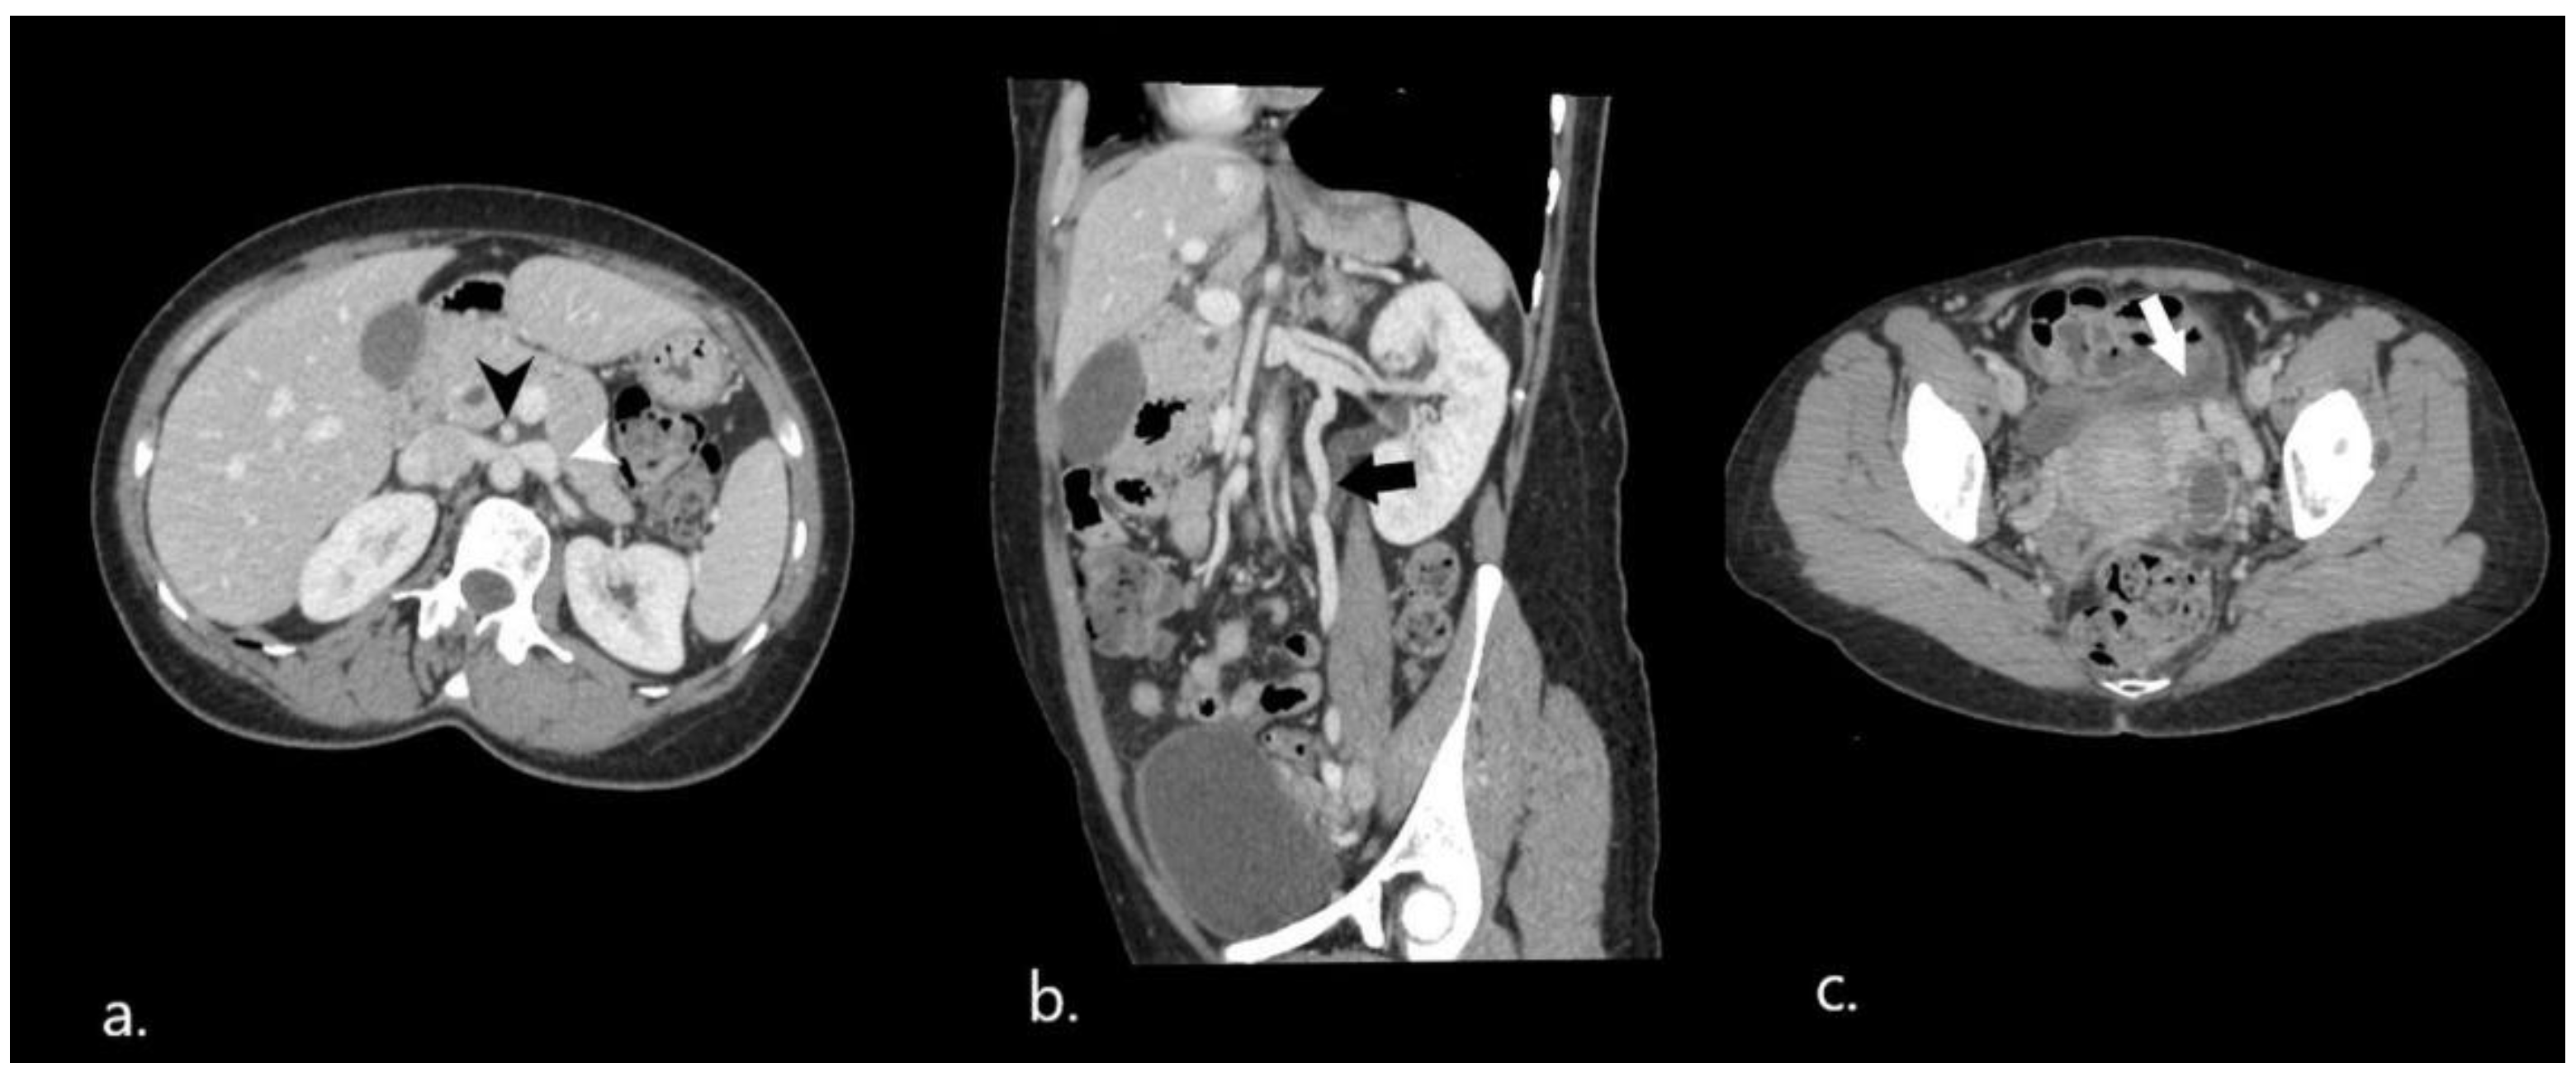

2. Case Presentation